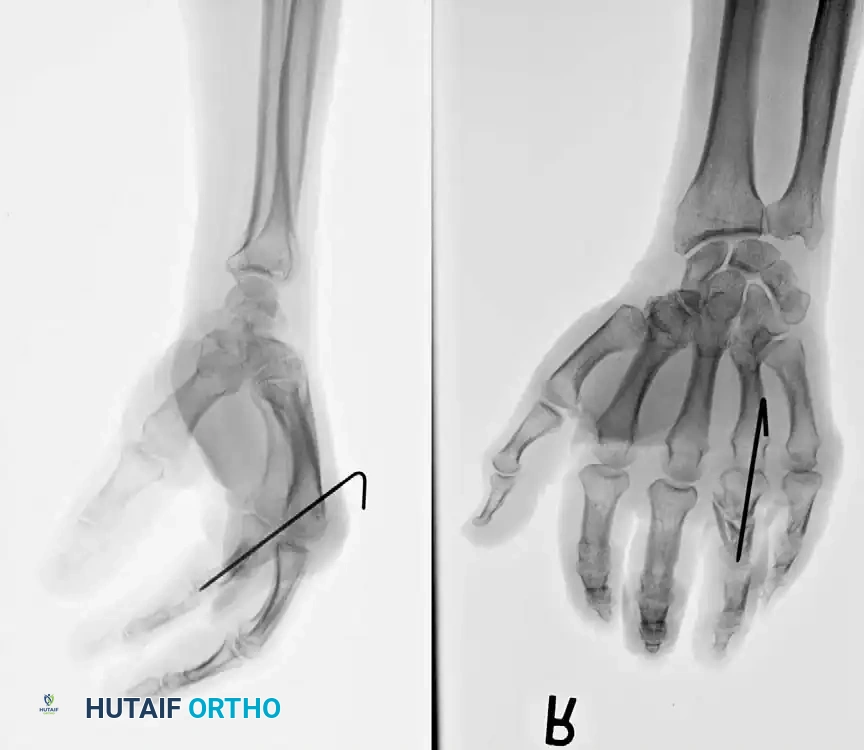

Percutaneous Techniques: Belsky-Eaton Pinning

Sometimes an unstable oblique fracture of a middle or proximal phalanx can be treated by closed reduction and percutaneous pinning. Belsky and Eaton described a highly effective technique for pinning multiple proximal phalangeal fractures without opening the fracture site.

Step-by-Step Technique:

* The fractured phalanx is held reduced with the MCP joint flexed to 90 degrees. This tightens the collateral ligaments, using them as a tension band to align the proximal fragment.

* A single K-wire is drilled from the dorsal aspect of the metacarpal head, passing across the MCP joint and straight down the medullary canal of the proximal phalanx to cross the fracture.

* Crucial Step: The wire must not cross the PIP joint.

* Leave the wire exposed proximally (bent outside the skin) to allow for easy removal in the clinic at 3 to 4 weeks.